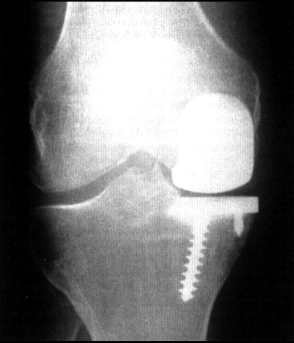

Example of a partial prosthesis

Partial prothesis. Only the iner part is replaced. We apply this procedure very rarely.